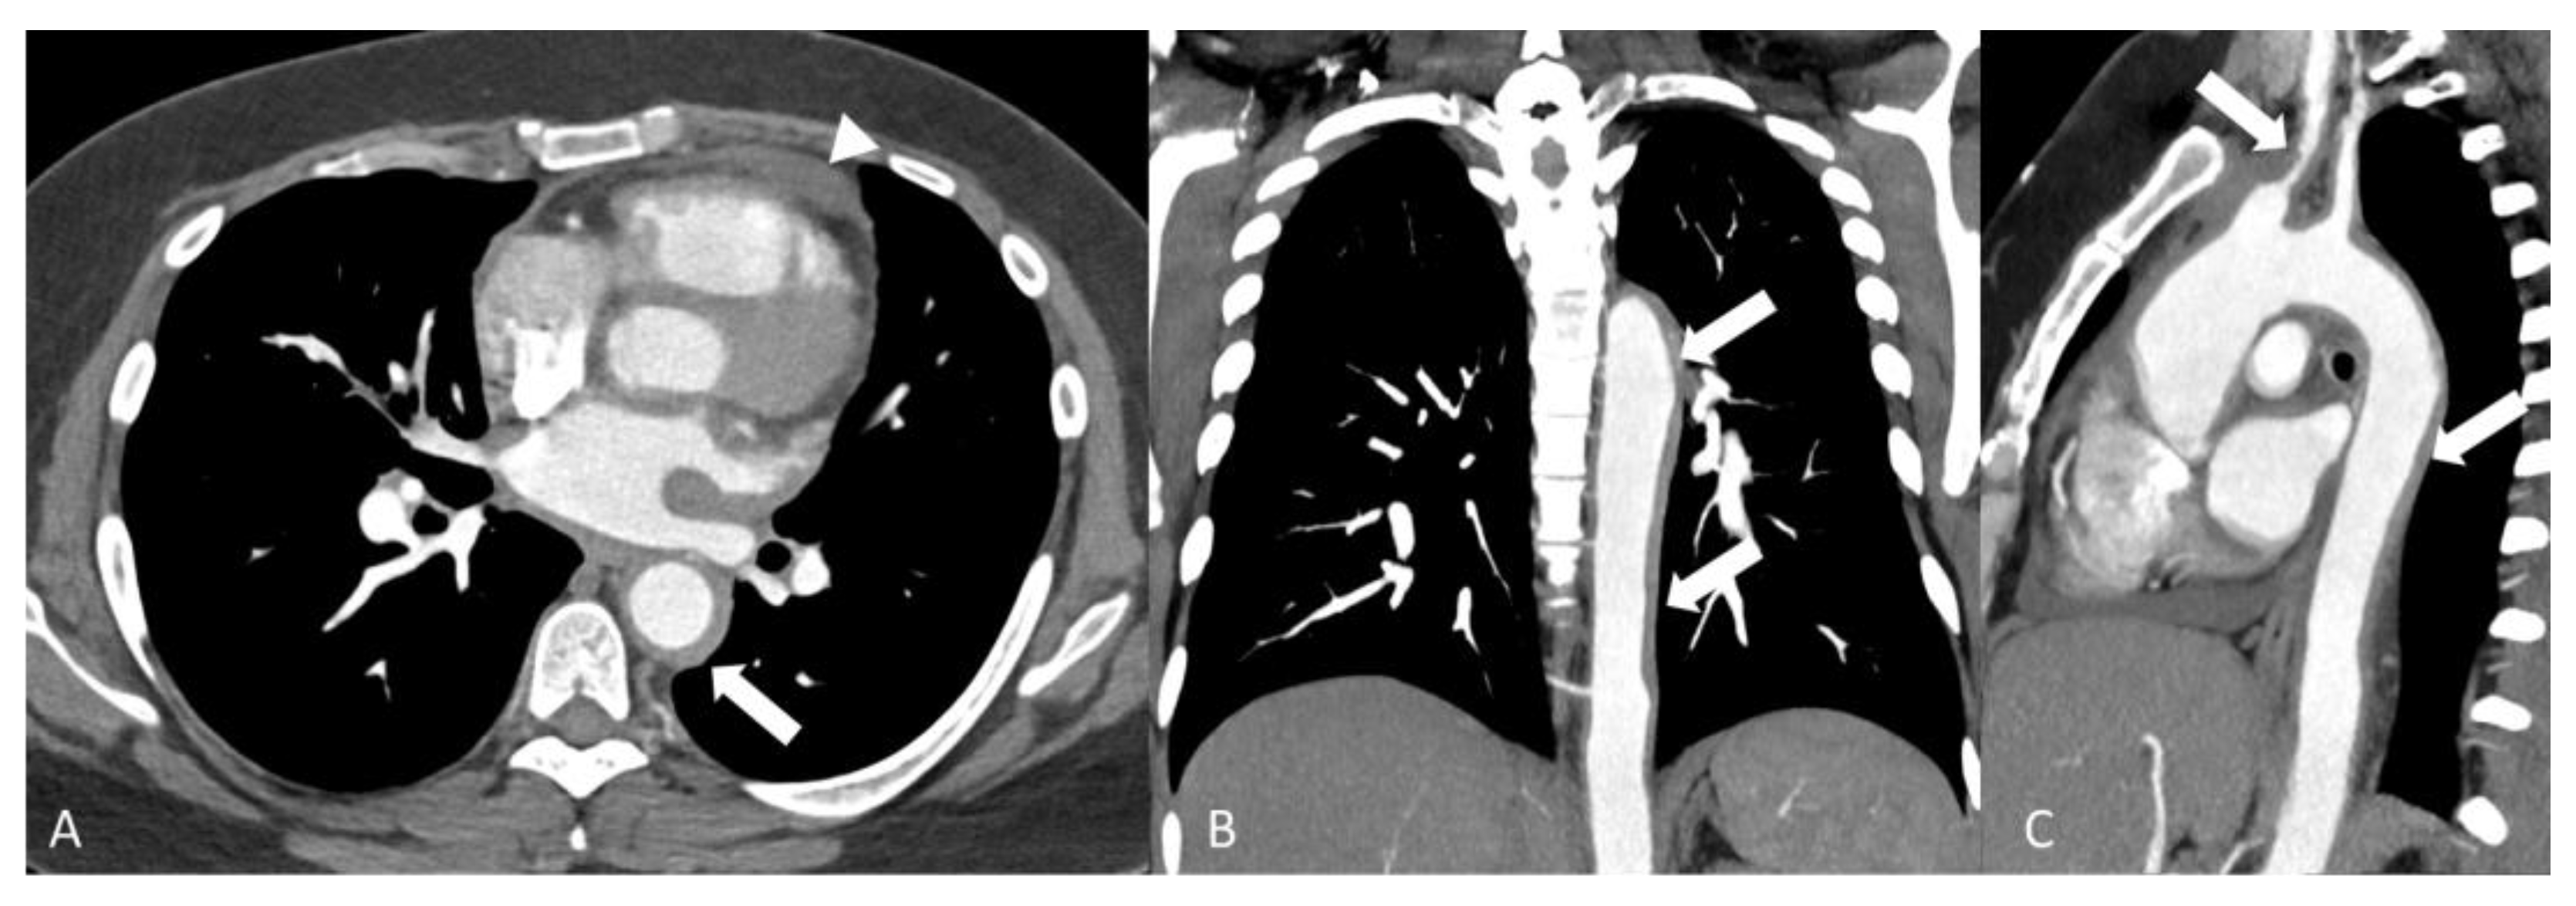

2.4.1. Behçet’s Disease

2.4.2. Cogan Syndrome